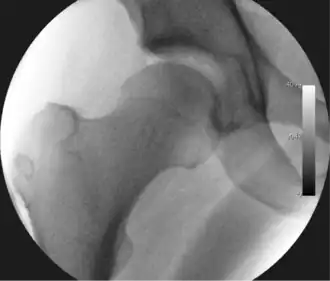

Figure 3. Fluoroscopic picture showing a mild amount of distraction of the hip before insertion of any instruments -

The procedure is performed with the patient asleep (general anaesthetic) or under spinal anaesthesia. There are two widely used methods, one with the patient on their back (supine) and the other on their side (lateral decubitus). Which is used is down to the surgeon's preference. To gain access to the central compartment of the hip joint (between the ball and socket), traction is applied to the affected leg after placing the foot into a special boot. (See fig. 2) There is specifically designed equipment for this, although some surgeons use a 'traction table', initially designed to help in the operative fixation of broken thigh and lower leg bones. The amount of traction (or pull) needed is assessed with the help of fluoroscopy (low-dose portable x-ray). (See fig. 3) It is usually not possible to distract the ball from the socket with traction alone by more than a few millimetres. Once the surgeon is happy that they will be able to gain access to the hip joint (i.e. the ball will distract from the socket by a small amount), the patient is then painted with antiseptic and the surgical drapes applied.